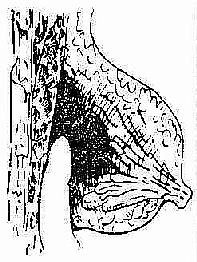

急性乳房炎脓肿形成期,治疗要则是及时切开引流,排出积脓。切开引流应注意如下要点:(1)为避免手术损伤乳管而形成乳瘘,切口应按轮辐方向作放射状切开,至乳晕处为止;深部脓肿或乳房后脓肿,可沿乳房下缘作弧形切口,经乳房后间隙引流之;既可避免乳管损伤,亦有利于引流排脓。乳晕下脓肿,应作沿乳晕边缘的弧形切口。(2)若炎症明显而未见波动处,不应消极等待,应在压痛最明显处进行穿刺,及早发现深部脓肿。(3)脓肿切开后,应以手指深入脓腔,轻轻分离其间的纤维间隔以利引流彻底。(4)为使引流通畅,可在探查脓腔时,找到脓腔的最低部位,别加切口作对口引流。(图2-12,2-13,2-14)。

图2-14 乳房深部脓肿的引流